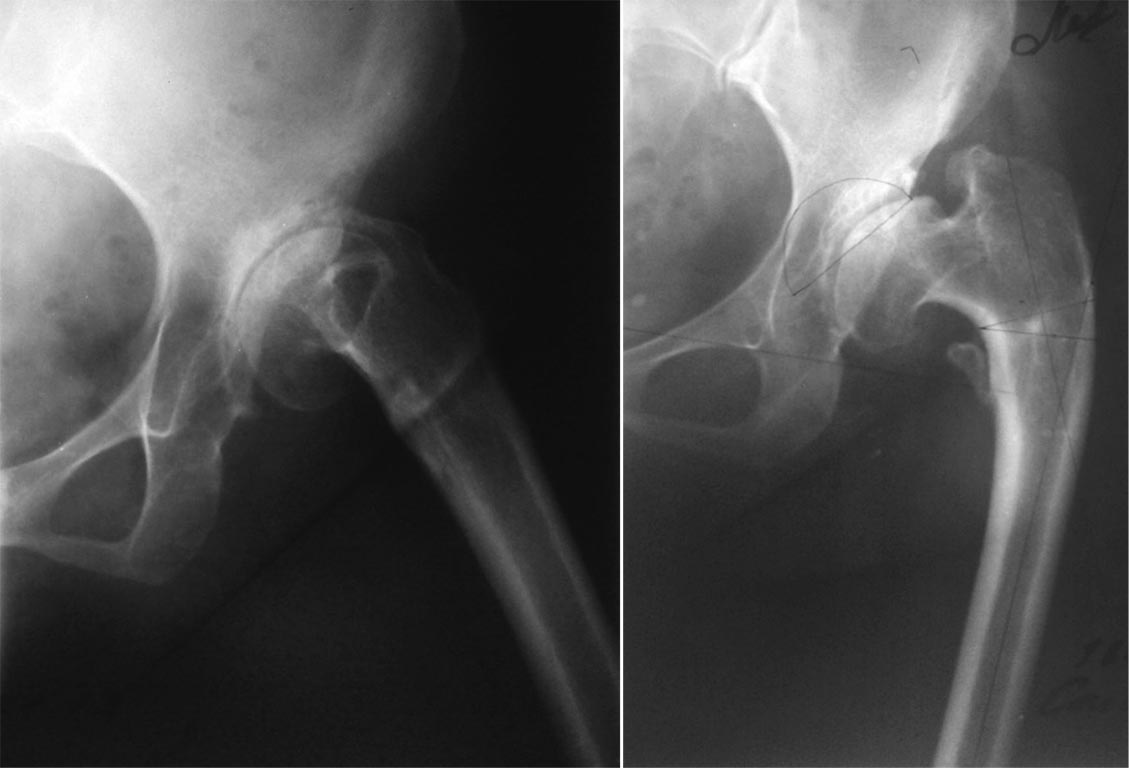

Мы в подобном случае  поступили следующим образом (укорочение тоже было

значительным, но обошлось без осложнений):